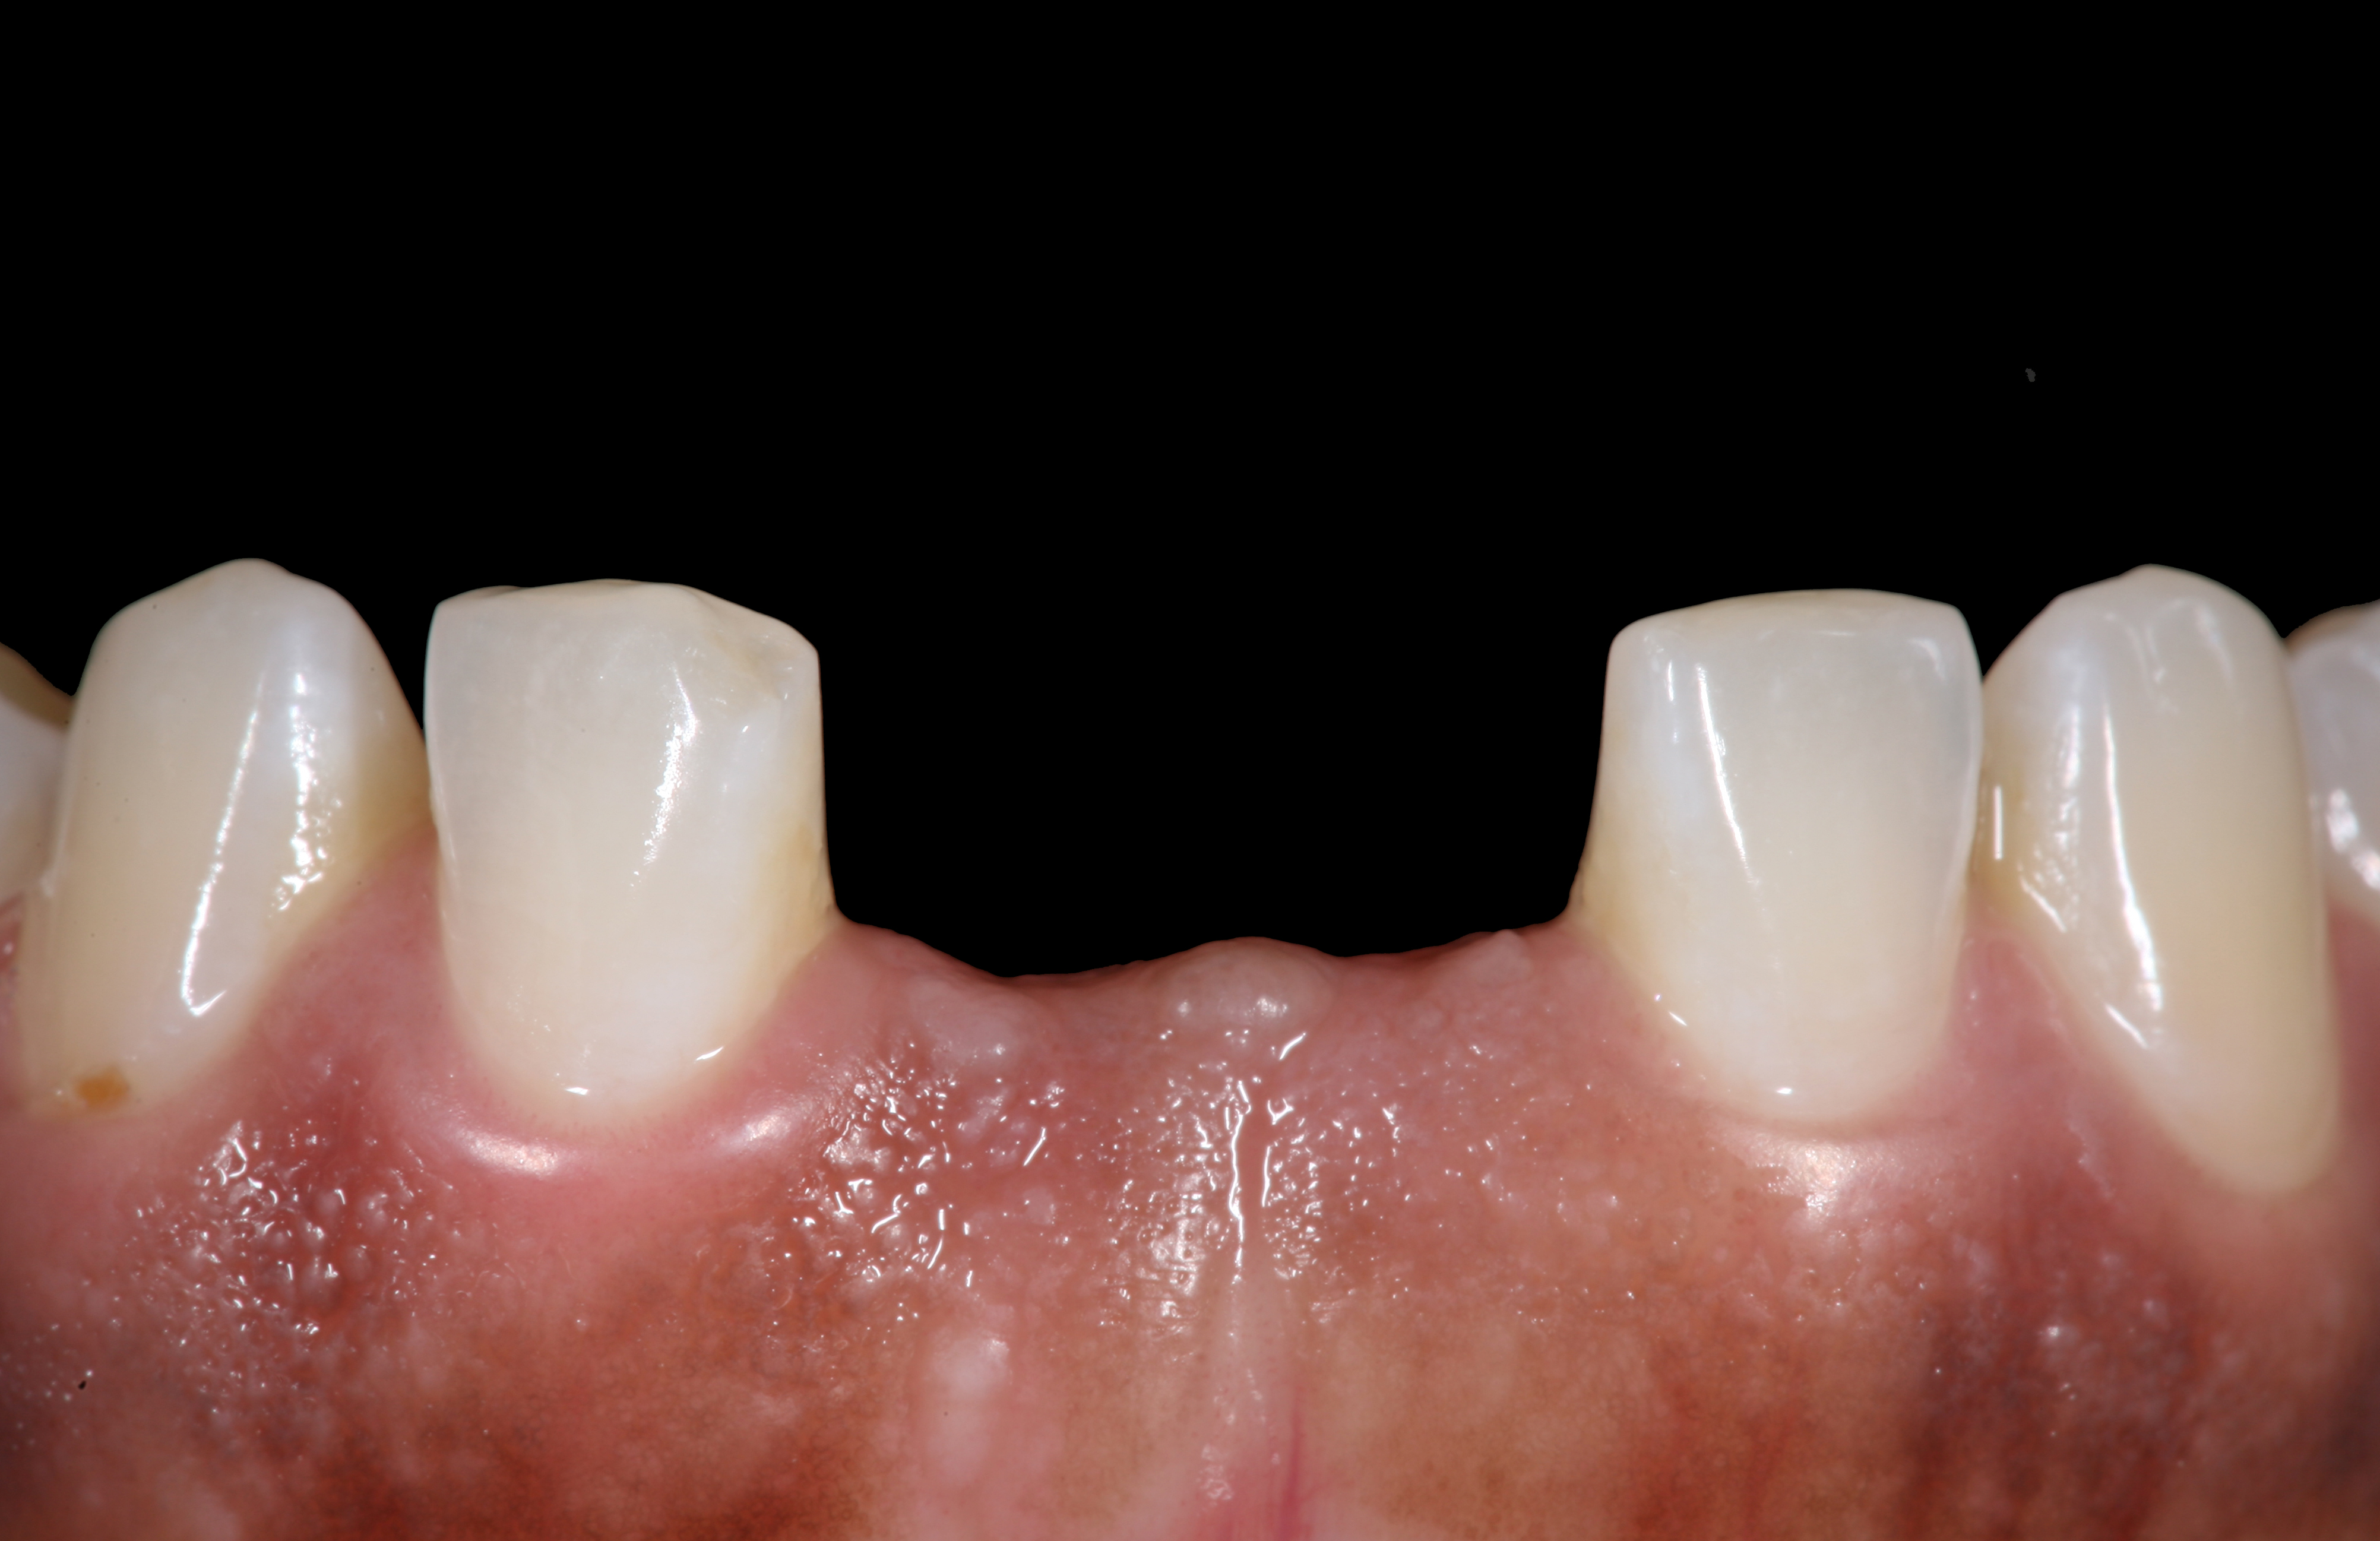

High-strength ceramic materials can be used in select cases to fabricate resin-bonded bridges to replace missing teeth as an alternative to removable prostheses or more invasive procedures such as conventional bridges or dental implants. The two missing lower central incisors (Figure 6) were replaced with two zirconia-based resin-bonded bridges (Figure 7). The single-retainer wing design has shown more than 94% clinical success after 10 years, which is significantly higher than the conventional two-retainer design (67.3% success).6 Proper bonding, however, is key for success and employs an air-particle abrasion step (Figure 8) followed by the application of a special ceramic primer (Figure 9). Figure 10 through Figure 12 demonstrate the clinical outcome.

Figure 6

Figure 7

The pretreatment situation.

Figure 13